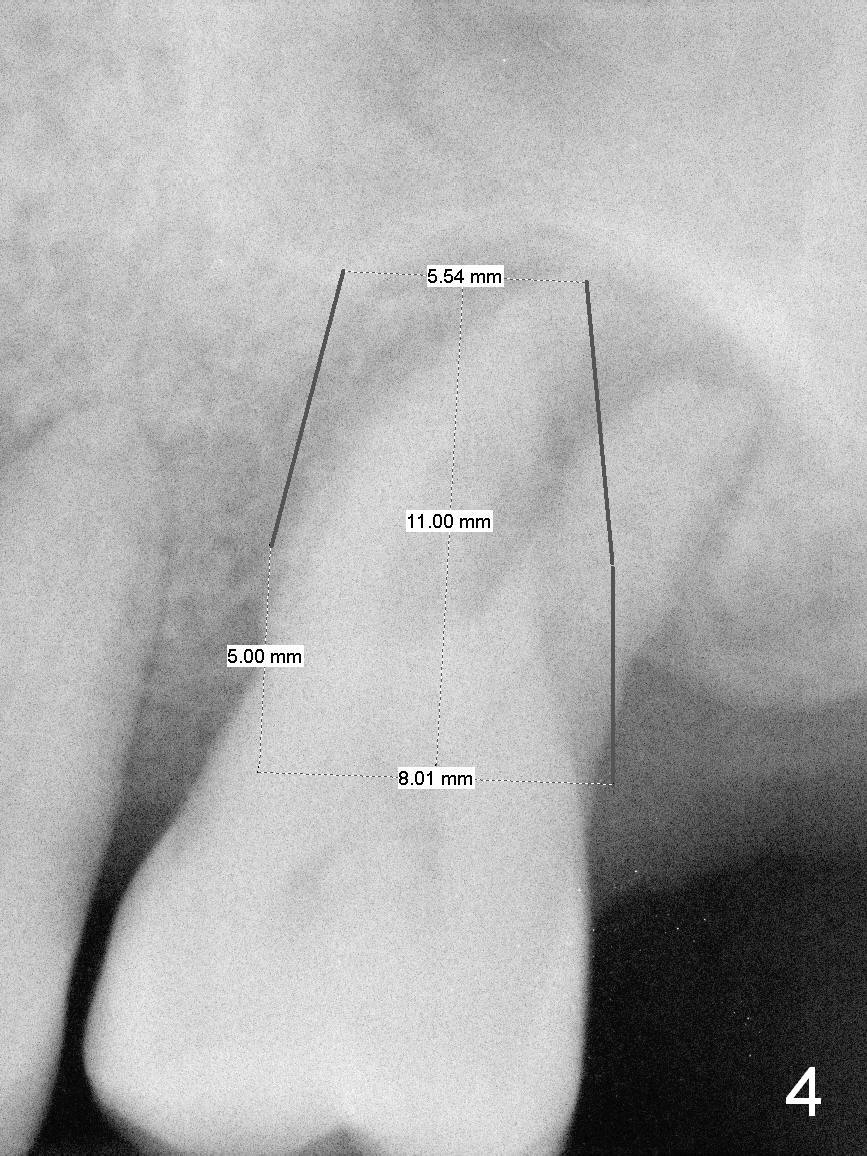

A large implant is place so that the mesiodistal dimension of the socket is obliterated by the implant (Fig.6 green circle). The buccal (Fib.5 B) and palatal gaps are filled with bone graft. It appears that either tapered (Fig4) or cylindrical (Fig.7) implant should be able to occupy the socket and obtain primary stability without perforating the sinus floor.